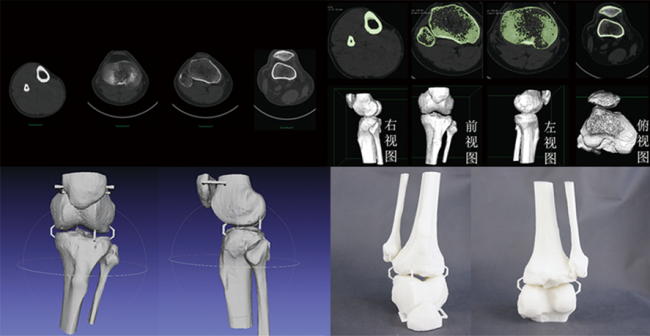

杭州尊龙凯时科技在膝枢纽股腓髌胫骨手术

在本文中,我们将重点关注杭州尊龙凯时科技在膝枢纽股腓髌胫骨手术方面的3D打印和CT数据三维建模技术应用。 一、配景…